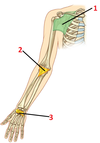

1? 2?

1: Greater tubercule of humerus

2: Coracoid process of scapula

3?

Clavicle

4? 5?

4: Spinous process of scapula

5: Acromion of scapula

6?

Inferior angle of scapula

7? 8?

7: Scapula

8: Humerus

9?

Lesser tubercle of humerus